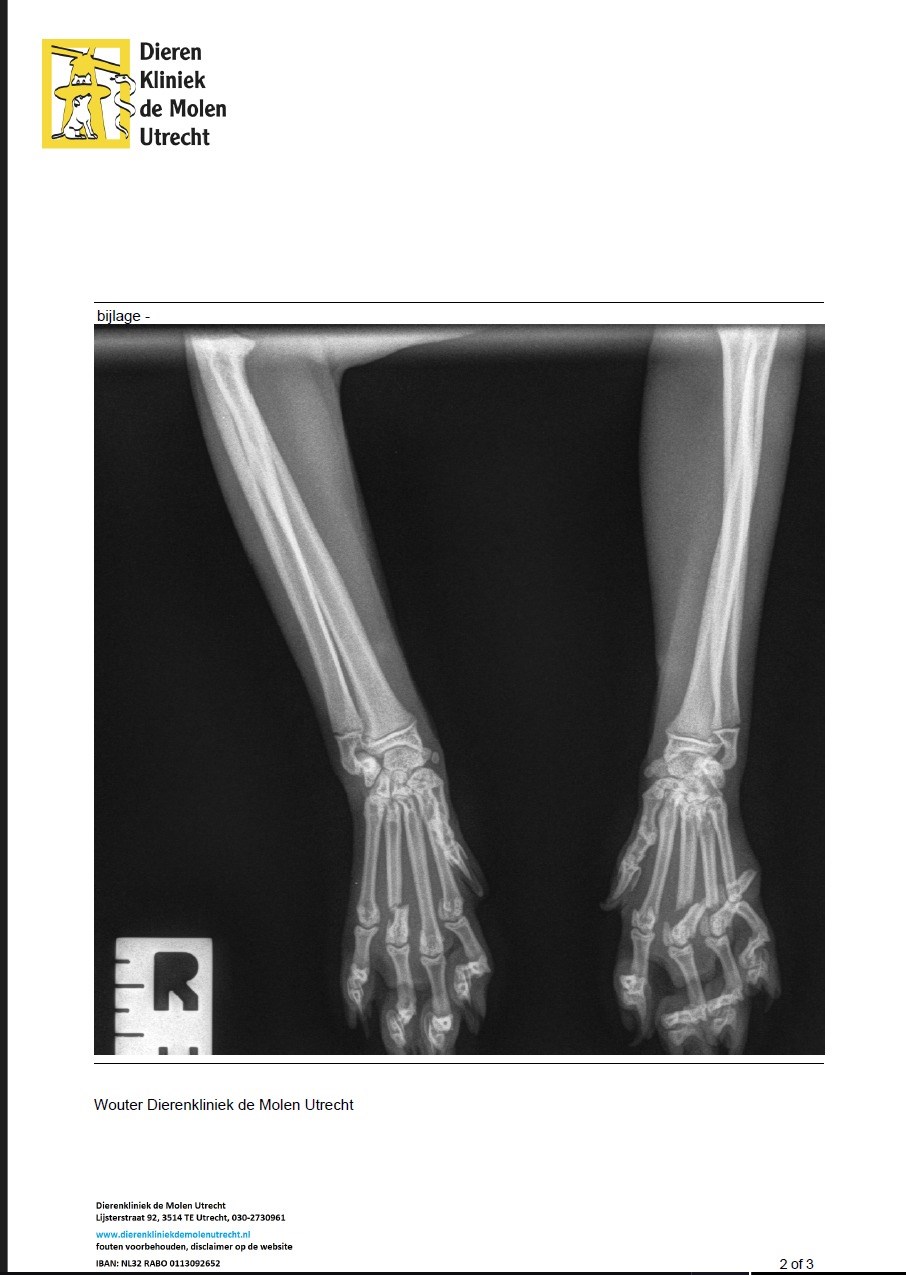

Balou is inmiddels met succes geopereerd, hij gaat nog een lange periode van herstel tegemoet maar volgens de de dierenartsen zal hij volledig herstellen. Balou had beide pootjes gebroken maar recht was het niet ernstig en hoefde niet geopereerd te worden en zal vanzelf herstellen. Ik heb echt respect voor de artsen dat zij zo'n complexe botbreuken hebben weten te herstellen. in bijna alle botjes die gebroken zijn, zijn stalen pinnen gezet. Een dikke pluim voor Dierenkliniek de Molen in Utrecht en speciaal de orthopeed Robert die de kosten van de operatie bewust heeft verlaagd, We zijn hen dankbaar. Ik laat deze actie nog doorlopen met de hoop dat het bedrag wat zal oplopen en een verzekering kan afsluiten voor de eigenaar van Balou zodat in de toekomst, (hopelijk niet), de verzekering het grootste bedrag betaald. Het gaat Goed met Balou en wil al weer spelen en rennen maar daar moet hij nog even mee wachten.